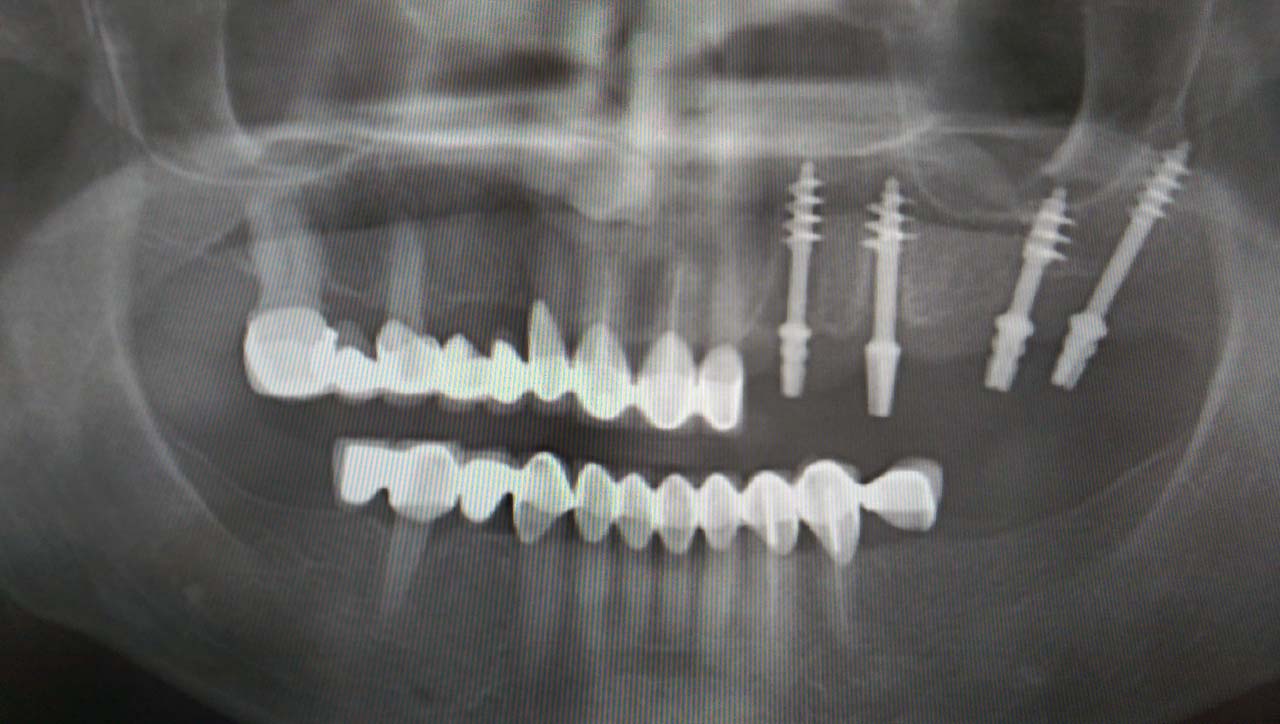

Teljes fogatlanság helyreállítása 2 nap alatt

Teljes fogatlanság helyreállítása 2 nap alatt azonnal terhelhető svájci IHDE implantátumokkal és PMMA műanyag hidakkal. Intraorális szkennerrel vettünk lenyomatot az implantáció után, és erre a digitális mintára készítette el a fogtechnika a hidak digitális tervezését, majd faragta ki műanyagból. Ezt a gyors munkát az azonnal terhelhető implantátumok és a digitális lenyomat, tervezés segítségével tudtuk megcsinálni mindössze 2 nap alatt. Dr. Kelemen Péter és a Symbion Fogtechnika munkája.